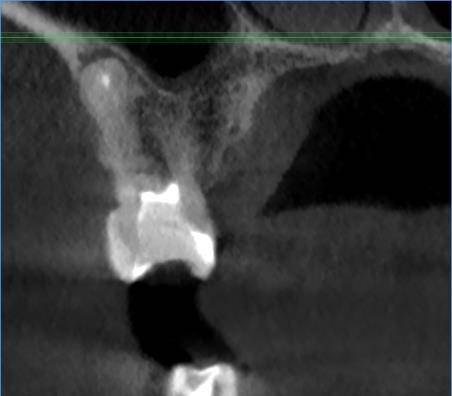

Есть зуб 11 (с СВШ) с восспалением около корня. До брекетов тоже было.

Перед протезированием предлагают перелечить каналы через корень с извлечением СВШ и последующим восстановлением (не понятно правда с СВШ или уже без него. Без СВШ зуб прям под корень может обломаться) под коронку.

До этого предлагали резекцию. Как в итоге лучше, через корень или резекцию?11-2.jpg.ba542aa82cfd6ddaad3fb9e234b99d99.jpg11.jpg.a34f40916e8e638d622001c50fff6e3a.jpg11-3.jpg.7a281f5893f8e6440937071fda10d523.jpg11-4.jpg.6a62c56e00cfdfa00cf35b7e276fd908.jpg